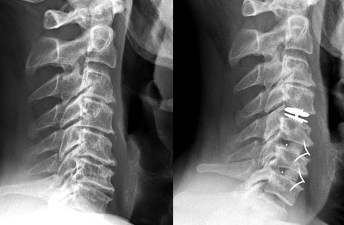

Let’s See PowerPoint : Anterior Cervical Surgery : Fusion versus Prosthesis

Let’s see : Cervical Disc Arthroplasty on 2 levels